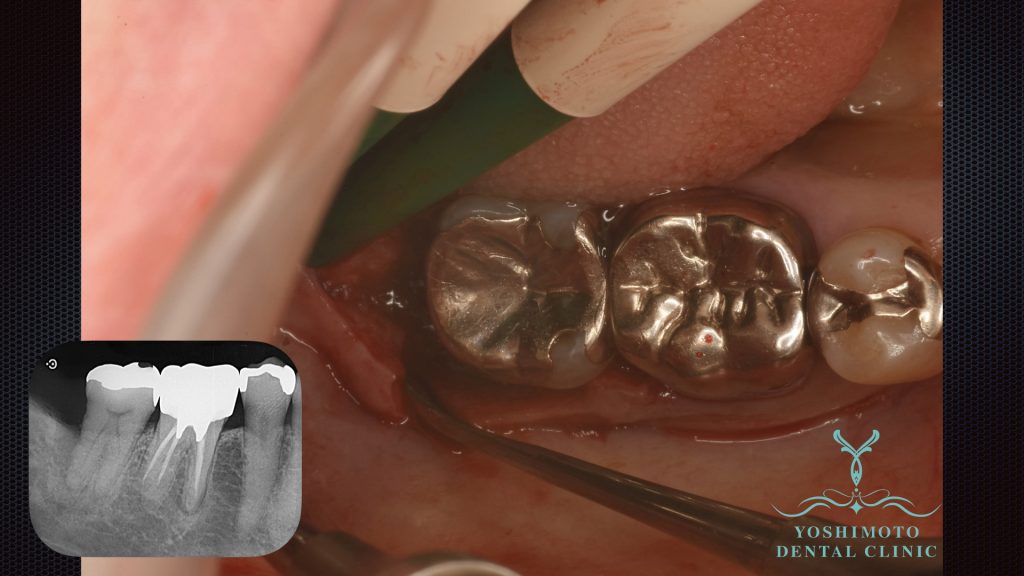

⇧歯周外科手術時の写真です。

レントゲン所見でも最後臼歯に垂直性の骨吸収が確認されました。

局所麻酔下にて切開を行い、歯肉弁を剥離し徹底的にデブライドメントを行い、リグロスによる歯周組織再生療法を試みました。